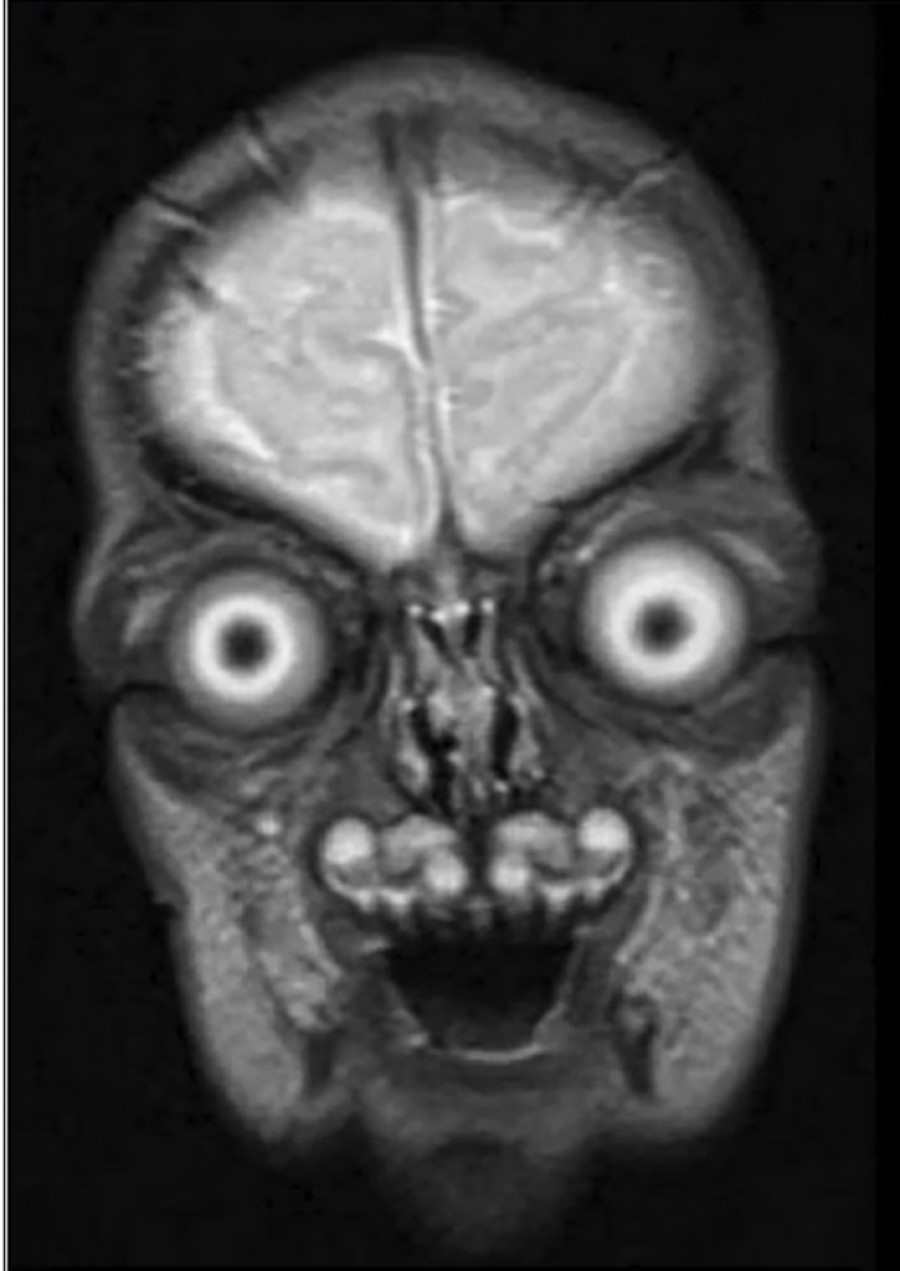

Sa pretećim očima i đavolskim osmehom, bilo bi vam oprošteno ako pretpostavite da su to samo vanzemaljci iz holivudskog naučno-fantastičnog blokbastera.

Ipak, verovali ili ne, nisu lažni, već originalni MRI skenovi ljudskih beba u materici. Izbezumljeni korisnici društvenih medija šalili su se kako su se užasnuli kada su videli snimke koje izazivaju noćnu moru, a koji su prvobitno objavljeni 2021. godine.

Slične slike su potvrđene kao legitimne i objavljene su u listovima Univerziteta Harvard.

Roditeljima se ne nudi redovno magnetna rezonanca tokom trudnoće i obično će se skenirati samo ako postoji zabrinutost za rast i razvoj deteta. MRI skeniranje se razlikuje od ultrazvuka i potrebno je samo ako majka ili nerođena beba to zahtevaju iz medicinskih razloga. Na primer, oni mogu pomoći u definisanju i otkrivanju malformacija vrata, grudnog koša, abdomena i kičme kod fetusa, prema bolnici Great Ormond Street.

Međutim, kada se koristi tokom trudnoće, magnetna rezonanca može da proizvede veoma životnu sliku njihove bebe. Detaljne crno-bele slike razbijaju iluziju mnogih roditelja koji slepo veruju da će njihovo dete biti divno. Korisnik Twittera je otišao korak dalje, pa je rekao da se magnetna rezonanca ne preporučuje tokom trudnoće jer bi „ljudi shvatili da inkubiraju demone iz noćnih mora i bili bi s pravom uplašeni“.

MRI mašina koristi i šalje magnetne i radiofrekventne talase u majčin stomak kako bi proizvela ove uznemirujuće slike nerođenih beba. MRI slike beba obično ne privlače istu pažnju na mrežama kao ultrazvučne slike, jer ovako detaljne slike mogu izgledati pomalo demonski.

Oni su potvrdili da su slike stvarne i razgovarali sa istraživačem sa Univerziteta u Viskonsinu, koji koristi MRI tehnologiju za proučavanje promena u mozgu koje su povezane sa uzrastom. On je rekao da se čini da su rezultati magnetne rezonance autentični.